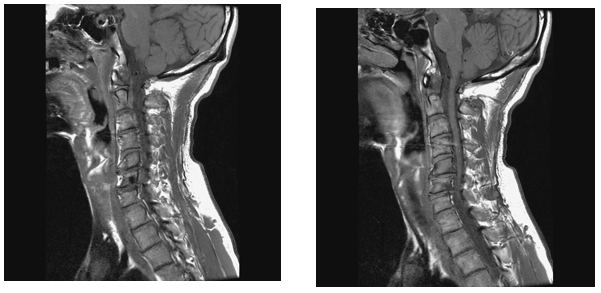

Clinical examination revealed tenderness confined to the neck and upper back, as well as tenderness in the lower back and sacroiliac joints. Cervical rightward rotation and left shoulder elevation were restricted. Laboratory tests showed a mildly elevated eosinophil count (8.0%). Imaging studies, including cervical spine AP and lateral X-rays, demonstrated C5-C7 intervertebral space narrowing and retrolisthesis. Tc-99m methylene disphosphonate (MDP) whole body bone scan with whole-body imaging was arranged, and localized imaging with single-photon emission computed tomography (SPECT)-CT for cervical-thoracic spines confirmed increased radiotracer uptake in the C6 vertebra, identifying a 0.7 cm cystic lesion (Figure 1). On T1-weighted images, the intervertebral disc was clearly seen herniating into the C6 vertebra, with the herniated portion connecting to the cavitated lesion (Figure 2A). Another image (Figure 2B) demonstrated the C7 vertebra compressing the intervertebral disc upward, causing partial rupture. On T2-weighted images, the cavity appeared hypointense (Figure 3A & 3B), and a distinct ring of sclerosis surrounds the cavity (Figure 3B), which is characteristic of Schmorl's cyst.4 Based on axial images (Figure 3C), it is suggested possible prior communication with cerebrospinal fluid. Furthermore, degenerative disc disease (DDD) was noted at C3-C4 and C4-C5, while C5-C6 and C6-C7 showed DDD with grade I retrolisthesis.

Figure 1 There was increased radiotracer uptake in the C6 vertebra.

In view of radiologic evaluation, proper image provided critical insights into the pathology. X-ray imaging revealed that the vertebral contour remained intact, with no evidence of aggressive bone destruction (not shown). On the bone scan, there was increased radiotracer uptake in the C6 vertebra (Figure 1), consistent with the first scintigraphic findings in Schmorl’s node.5 MRI images showed the intervertebral disc herniating into the C6 vertebra, with the herniated portion connecting to the cavitated lesion (Figure 2A & 2B), and the C7 vertebra compressing the intervertebral disc upward, causing partial rupture. Also, the cavity of C6 appeared hypointense (Figure 3A & 3B), with a distinct ring of sclerosis surrounds the cavity (Figure 3B), which is characteristic of Schmorl's cyst.4 MRI findings further clarified the pathology of Schmorl’s node, which typically appears a small bony notch filled with herniated disc material in the upper or lower endplate of a vertebral body.6

In the field of scintigraphic rehabilitation, bone scan together with SPECT-CT can be utilized as the first line to detect pathology, particularly useful in the localization of the exact site of pain/tender area.17–31 for instance, early inspection of cavitation in the C6 vertebra with increased uptake, like our case. After all, images with function are far better than images with only structure. What's more, SPECT-CT has both functional and structural images, which will prevent clinicians from misdiagnosing.